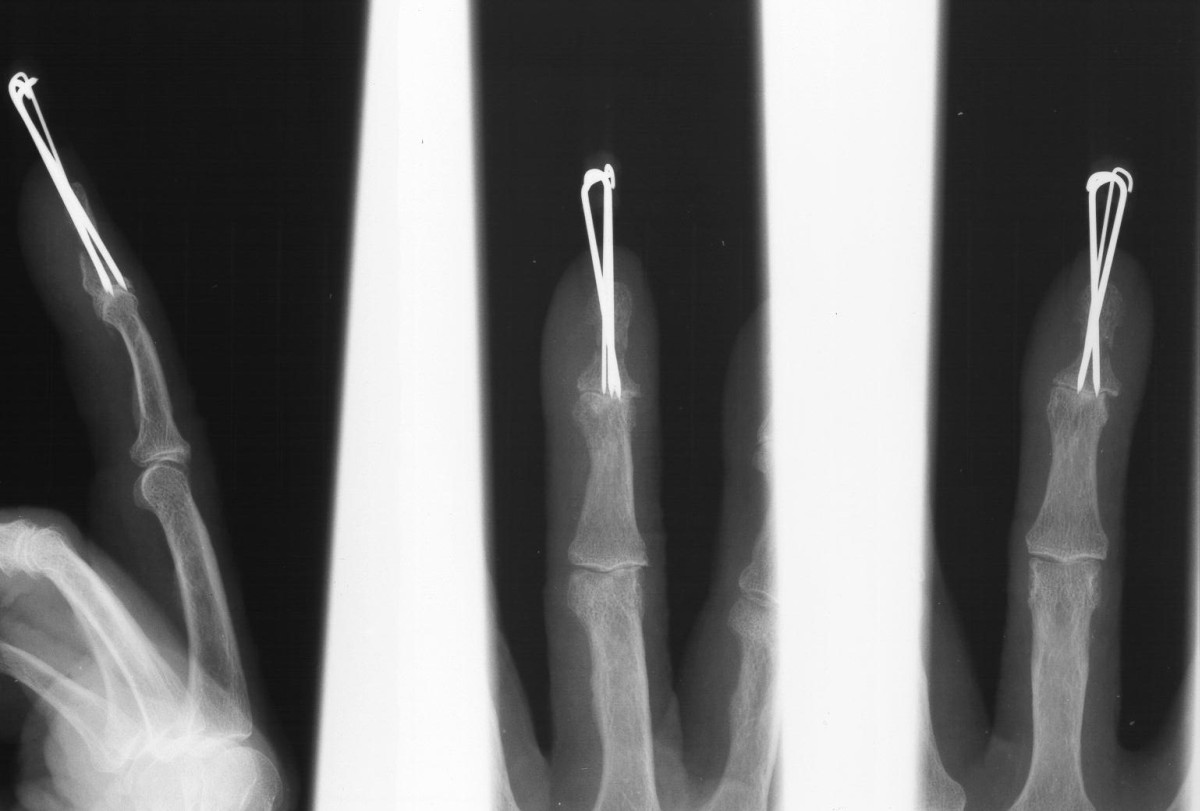

Case 3

Acute mallet fracture treated with percutaneous

pinning: proximal pin stabilizes the fracture

fragment, longitudinal pin maintains distal phalanx

position. |

| Thermoplastic bonding of the protruding ends: appearance at one month. |